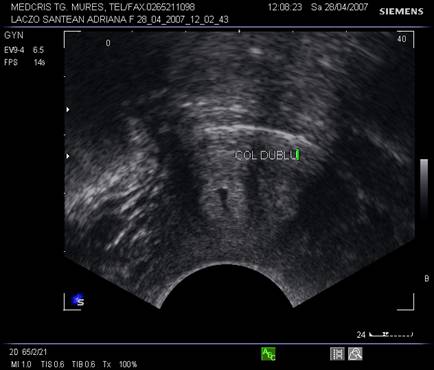

Fig. nr. 100. Sectiunea transversala la ecografia vaginala a pacientei cu uter dublu, col dublu, indica prezenta a doua canale cervicale separate (sageata)